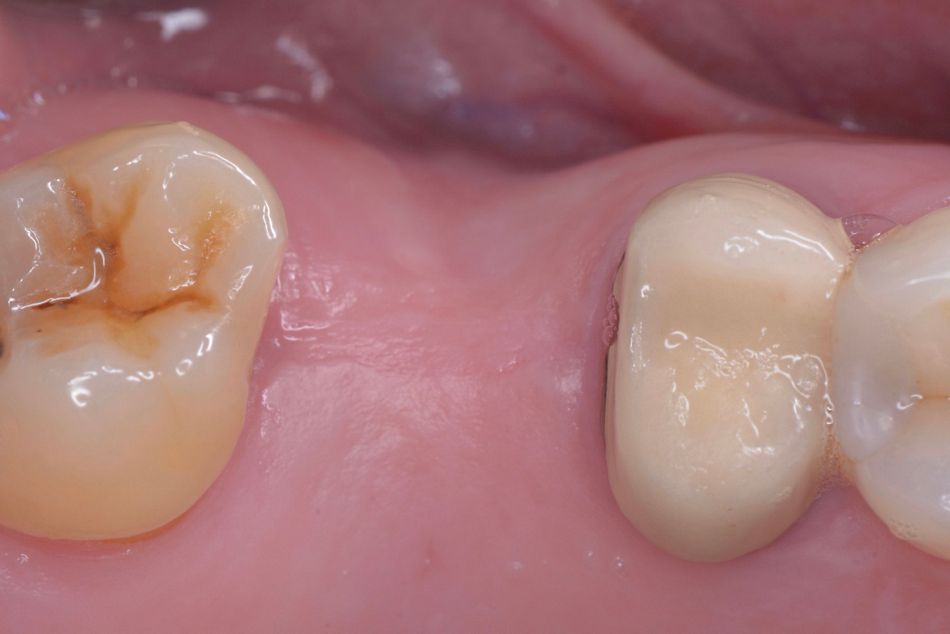

The patient was scheduled for regular follow-up visits and, at the five-year follow up, the prosthetic restoration continued to function effectively without any complications related to the implant or abutment. The soft tissues remained healthy, and the occlusion was well-aligned. The patient reported high satisfaction with both the functional and esthetic outcomes, highlighting the long-term success and stability of the treatment (Figs. 30-32).